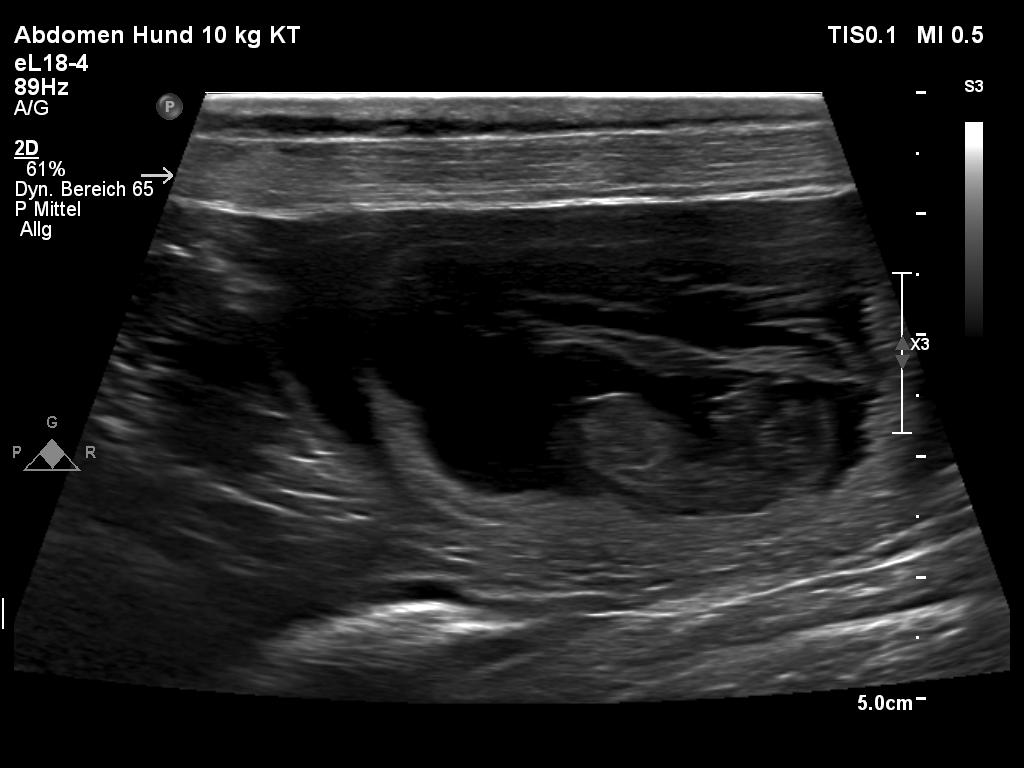

Heute waren wir beim Tierarzt zur Ultraschalluntersuchung.

Juhu - Jette ist tragend!!!! Die Welpen werden um den 03. Oktober 2025 erwartet.